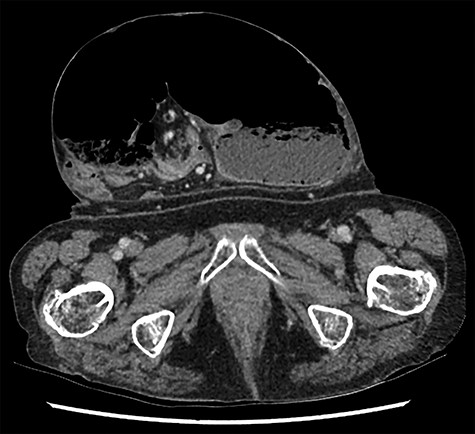

Caecal volvulus through wide-necked abdominal wall defect with small amount of free fluid in pelvis (sagittal).

A clinical diagnosis of bowel obstruction was made; she underwent a CT abdomen/pelvis with contrast, which demonstrated a large bowel obstruction within the hernia not caused by the hernial defect but thought likely due to volvulus of the caecum (Figs. 1 and 2).